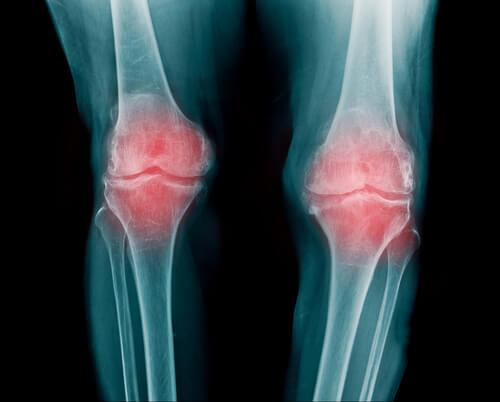

關節是兩個或更多個骨頭或是骨頭和軟骨的末端聚集在一起的部位。它們讓你的身體可以移動;基本上,它們讓你的手臂、腿和背部得以彎曲和轉動。

在構成關節的骨骼之間,存在著柔韌的彈性組織:關節軟骨。軟骨可防止骨骼之間摩擦,作為緩衝或襯墊的作用。

關節被一個支撐整個系統的“關節囊”包圍,而它則由韌帶支撐,防止關節輕易地受損。

- 類風濕性關節炎是關節的炎症,可能會影響數個不同的關節,一般來說會出現在手指、手臂和膝蓋。

- 它通常在30~60歲之間開始,而且在女性比男性中更常見,其發病率在種族和居住地之間沒有差異。

- 患有類風濕性關節炎的人行動力會降低,刺痛之後,就開始了糟糕的疼痛。